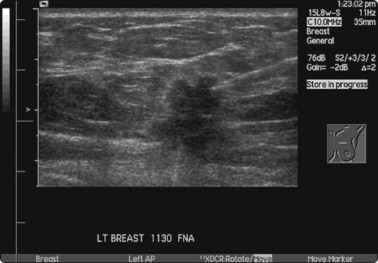

image

Fig. 3.5 FNA biopsy of a breast lesion with aggressive features

Several passes may be necessary to yield sufficient cells.

Many operators prefer US guidance for its speed, flexibility and real-time facilities. The patient is also able to lie comfortably during the procedure. The method is limited by the type of lesion; many microcalcifications are not visible on ultrasound examination. There is also the slight risk of pleural puncture or pneumothorax if used by inexperienced operators. The needle should run parallel to the chest wall and never be introduced perpendicular to the ribcage (see Fig. 3.4). By positioning the patient and compressing the breast, the depth of the lesion can be reduced. Breast lesions often require multiple sampling, typically best achieved using ultrasound guidance (Fig. 3.5).